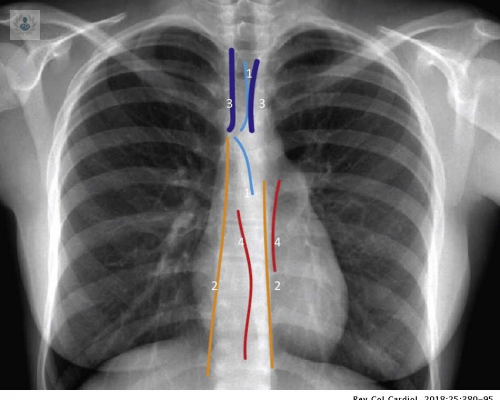

¿Cómo se diagnóstican las Enfermedades del Mediastino?

Las pruebas de imagen diagnóstica son muy útiles para detectar las Enfermedades del Mediastino. Los especialistas afirman que son una forma no invasiva y totalmente indolora para poder visualizar imágenes de órganos e identificar eventuales anomalías en el cuerpo del paciente